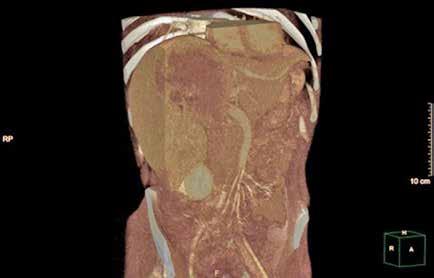

Localizada en los segmentos VII, V y parte del IV, entre las venas suprahepáticas (VSH) derecha y media, contactando con ellas en su origen. Caudalmente llega hasta la bifurcación hiliar, cercano a la bifurcación portal. Esta masa presenta una captación periférica en fase arterial y algo más isodensa en fase venosa y tardía, con un área central heterogénea e hipodensa en estas últimas fases. Con este comportamiento radiológico, se establece un diagnóstico de sospecha de hepatocarcinoma fibrolamelar o adenoma. Como variante anatómica, se objetiva una arteria hepática que nace de la arteria mesentérica superior (Figura 1). El paciente es ingresado en Digestivo para estudiar la lesión. Se realiza una Resonancia Magnética (RM) y se establece un diagnóstico de sospecha de hepatocarcinoma fibrolamelar (Figura 2). Se descartó una biopsia por el riesgo de resangrado que presentaba. La alfafeto proteína solicitada durante el ingreso fue normal. Dado que se trata de una lesión hepática sintomática y que ha presentado un sangrado, está indicada la resección de la lesión, pero su tamaño y localización lo impiden. La lesión está tan cerca de las VSH que resulta imposible disecarlas y seccionarlas con seguridad, siendo imposible la cirugía. Se comenta el caso en el comité multidisciplinar y se decide embolizar la tumoración con el objetivo de evitar un nuevo sangrado y disminuir su tamaño para separarla de las estructuras vasculares. Se cateteriza la arteria hepática, desde la mesentérica superior. Se emboliza con micropartículas

Figura 2 (A y B).

RM: Gran masa hepática localizada en segmentos VII, V y parte del IV. Comportamiento radiológico característico de hepatocarcinoma.

A) T1, imagen hipointensa entre VSH derecha y media.

B) T2, lesión hiperintensa con centro hipointenso.